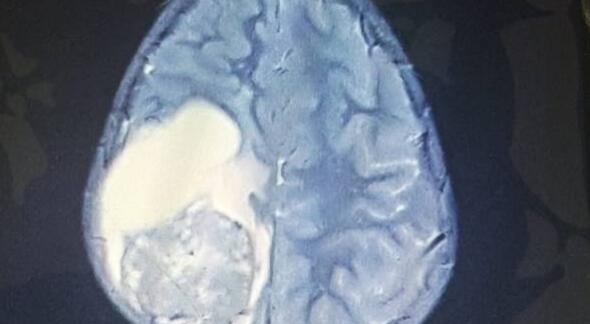

核磁共振显示,Paige大脑右侧的肿瘤已经蔓延至脊柱,如果不立即做脑部手术的话,她可能只剩下几天的时间,而手术的风险也极高,家人立即同意第二天为Paige进行脑部手术。